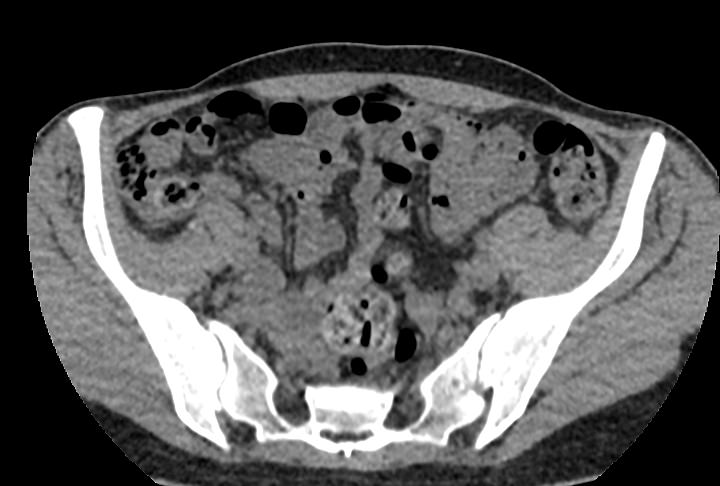

Мультиспиральная компьютерная томография позволяет детально оценить структуру лимфатических узлов, выявить ее неоднородность, определить точные размеры, выявить деформацию контуров, появление инфильтрации окружающих тканей с образованием цепочек, пакетов и конгломератов лимфоузлов.

Мультиспиральная компьютерная томография позволяет оценить структуру лимфатических узлов, обнаружить неоднородность, гиперплазию, деформацию их контуров.

Мультиспиральная компьютерная томография дает возможность визуализировать размеры лимфоузлов, их точную локализацию, взаимодействие с близлежащими органами и окружающими тканями, образование спаянных между собой инфильтратов лимфоузлов, выявить прорастание в окружающие ткани.